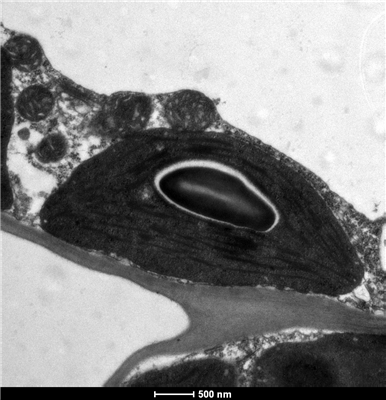

透射電子顯微鏡(Transmission Electron Microscope,TEM)是使用頗為廣泛的一類電鏡。通過發射電子束從而穿過超薄的樣品,同時與樣本相互作用,既而形成圖像。透射電鏡H-7650是一臺高分辨率成像儀器,使用雙狹縫物鏡,可以得到獨有的低倍大視野,高對比度成像的特點,配有高靈敏度CCD相機,具有低劑量電子束成像的功能;具有更多的自動化功能,如自動聚焦,自動消像散,自動拍照等;具有圖像數據功能,測長,圖像過濾功能,具有較強的拓展功能。